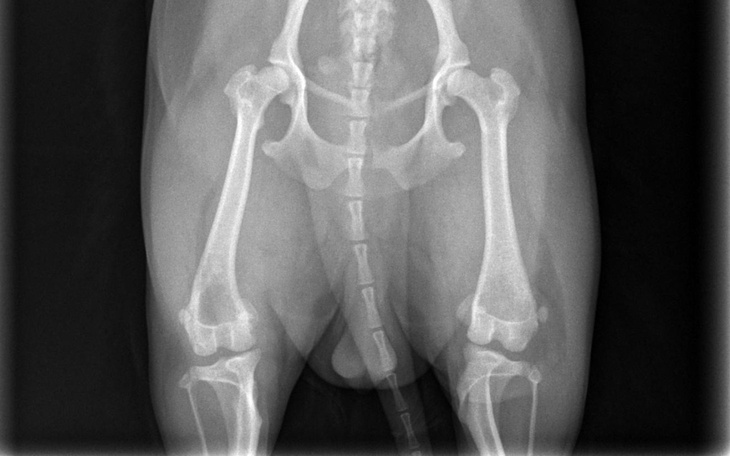

Każde z tych zwierzątek to dla mnie członek rodziny, moje codzienne wsparcie i ogromna radość. Niestety, los nie był Lady dla łaskawy. Zdiagnozowano u niej chorobę ganetyczną, obustronne zwichnięcie przyśrodkowe rzepek II stopnia w obu tylnych łapkach.

Oznacza to, że każdy krok sprawia jej ból. Czasem podnosi łapki, unika chodzenia i piszczy z bólu, a ja widzę, jak bardzo się męczy… 💔

Lekarze jasno powiedzieli, że bez operacji jej stan będzie się pogarszał. W każdej chwili jej tylne łapki mogą stać się całkowicie niesprawne… To myśl, która łamie mi serce.

Jedyną szansą na normalne życie bez bólu i ograniczeń jest operacja obu tylnych łapek, trzeba je złamać, odpowiednio ustawić i ustabilizować. Szacowany koszt zabiegu to około 15 000 zł, dodatkowo koszty rehabilitacji i leczenia, co niestety przekracza moje możliwości finansowe.